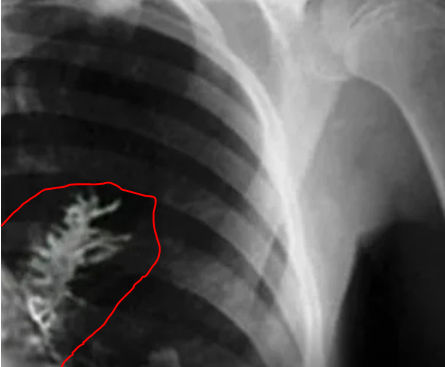

El médico realizó una radiografía y descubrieron una masa en su pulmón izquierdo, los especialistas creyeron era un tumor.

El jefe del Centro de Oncología de Udmurtia, Vladimir Kamashev, revisó la radiografía y estaba seguro que era cáncer. Él expresa que en el fondo sentía que algo andaba mal, que aunque había visto miles de radiografías similares, algo era diferente.

Ya en la mesa de operación antes de extraer la mitad del pulmón ya que era la única solución para eliminar el “tumor” decidio verificar una vez más. Kamashev decide hacer una incisión en el pulmón y es donde todos se llevaron la sorpresa de sus vidas. La masa extraña no era un tumor, era un árbol de 5 cm de largo.